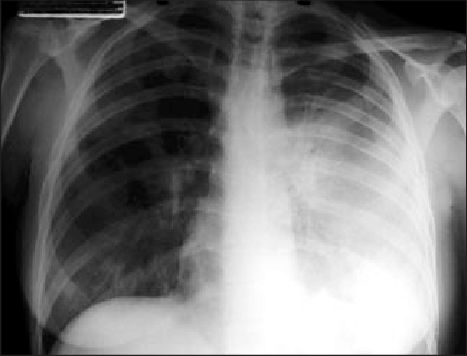

กาฬโรคปอดผู้ป่วยจะมีภาวะปอดบวม หายใจลำบาก เจ็บหน้าอก อาจมีน้ำมูกหรือเสมหะเป็นเลือด และอาจรุนแรงถึงขั้นระบหายใจล้มเหลว กาฬโรคปอดนั้นเป็นกาฬโรคชนิดเดียวที่สามารถส่งต่อจากคนหนึ่งไปอีกคนได้

ลักษณะปอดที่ติดเชื้อ By CDC - https://www.cdc.gov/plague/symptoms/index.html, Public Domain, https://commons.wikimedia.org/w/index.php?curid=63934944